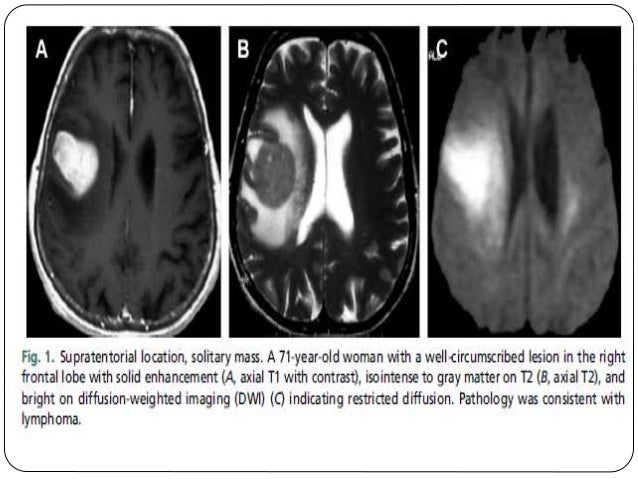

Adult Brain Tumors | Radiology Key

Adult Brain Tumors | Radiology Key from i0.wp.com

A brain tumor is a mass of abnormally growing cells in the brain or skull. Any growth inside such a restricted space can cause problems. Brain tumors are masses of abnormal cells within the brain.